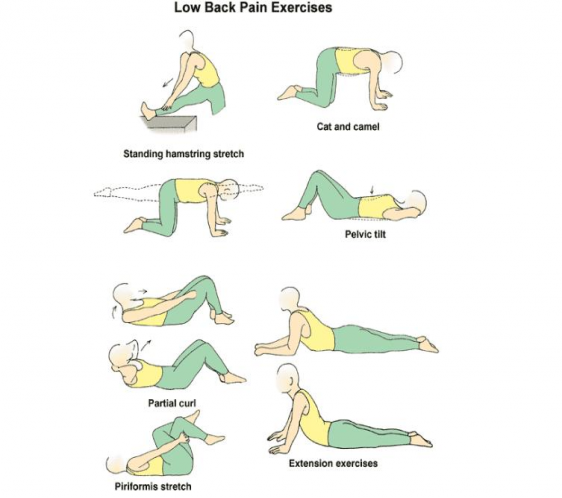

7 Herniated Disc Exercises For Lower Back (Lumbar Area) | Herniated …

Yoga For Bulging Disc Lower Back | Kayaworkout.co

2 Powerful Ways to Reverse a Bulging Disc in Lower Back

How To Heal A Bulging Disc With Exercise

Herniated Disc Exercises for Fast Results- Lower Back Pain Relief

Back Exercises: Bulging Disc Lower Back Exercises

Herniated Disk Exercises Lower Back – 17 Best images about The back on …

Exercises for a Bulging Disc in the Lower Back | Bulging disc, Lower …

Back Strengthening Exercises: Lower Back Strengthening Exercises For …